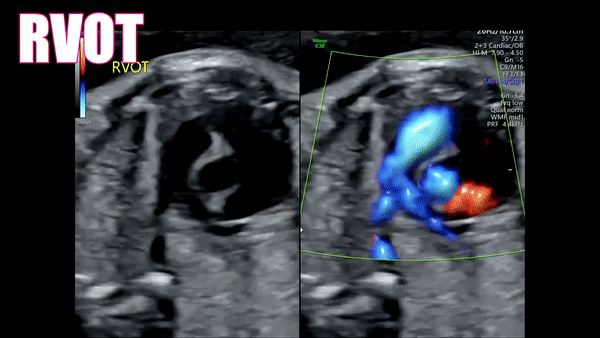

4th: RVOT

As you focus on the right ventricle it should be obvious by the moderator band. The Right ventricle is also the most anterior portion of the heart. The RVOT comes off of the right ventricle and points towards the fetal left shoulder. As you follow the RVOT, angle your transducer towards the fetal left shoulder. You should see the tricuspid valve and the Pulmonary valve. The RVOT should then bifurcate into the Ductus Arteriosus and the Right Pulmonary artery.